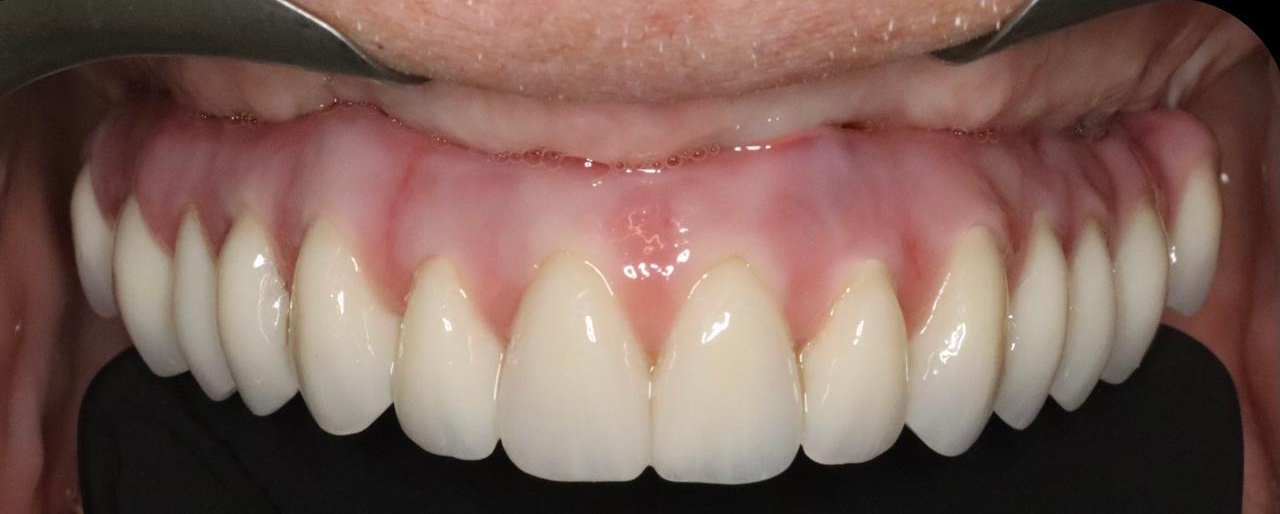

After the healing period, we moved forward with the final fixed implant-supported bridge. The final prosthesis was carefully designed to restore natural tooth anatomy and provide a harmonious, lifelike smile that perfectly complements the patient’s facial features.

The transformation has been nothing short of remarkable. The patient, who had once been embarrassed and self-conscious, now has a bright, confident smile that she proudly shares everywhere she goes. She is overjoyed with the results and continues to radiate confidence in her daily life—no longer worrying about loose teeth or removable dentures.

“I used to be so embarrassed to even laugh in front of my friends. Now, I can’t stop smiling!”

“The day I walked out with my new teeth was the first time in years that I felt like myself again.”